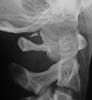

Spot Lateral

I cannot make a diagnosis from these films (which are clearly reproduced, I cannot decipher the information). There is a bony ossicle (?fx fragment) posteriorly between O-C1 and asymmetry of the atlas on open mouth odontoid. I would keep her neck braced and follow the clinical exam; probably with additional studies of the O-C1junction (CT +-MRI) and review with radiologist.

MRI was unremarkable except for showing the bony ossicle. Radiologists said the peg view was rotated.

Our radiologists tell me its part of a congenital arch. I have never seen this kind of remnant at this level. Has anyone else?